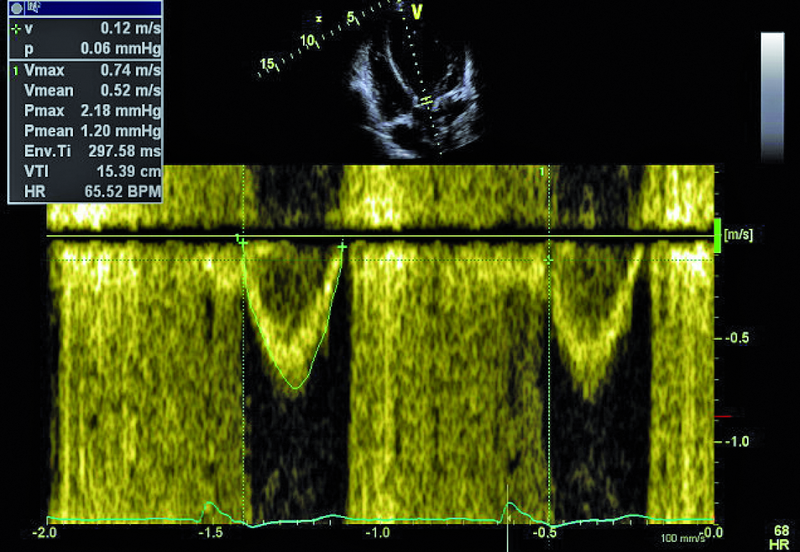

Kobieta, lat 41. Jakie patologie można rozpoznać na zamieszczonych rycinach?

1. Koarktacja aorty (ryc. 1).

4. Ciężka dysfunkcja skurczowa lewej komory (ryc. 3-5).

5. Niedomykalność zastawki aortalnej (ryc. 5, 6).